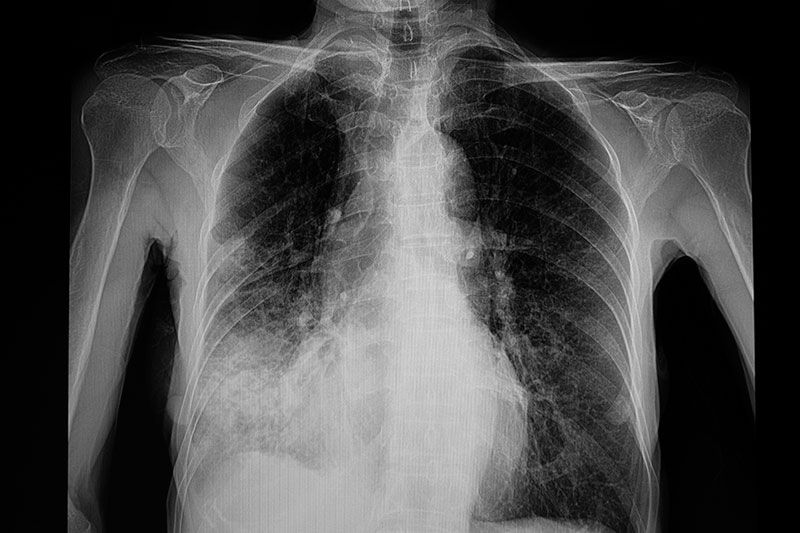

อย่างไรก็ตาม หากเป็นแล้วเสี่ยงเสียชีวิตหรือไม่ คนที่เสียชีวิตด้วยโรคปอดบวมนั้น สาเหตุส่วนใหญ่มาจากปอดมีการอักเสบรุนแรงและติดเชื้อในกระแสเลือด เนื่องจากได้รับการรักษาช้า รวมถึงยังเป็นผู้ที่อยู่ในกลุ่มเสี่ยงเบื้องต้นตามที่กล่าวมา แต่แท้จริงแล้วโรคปอดบวมเป็นโรคที่สามารถรักษาให้หายขาดได้หากได้รับการรักษาที่ทันท่วงที หากใครที่มีอาการเข้าข่ายแพทย์จะทำการเอกซเรย์ปอดเพื่อหาความผิดปกติ โดยสังเกตได้จากปอดจะมีฝ้าสีขาวอย่างชัดเจน แต่ในผู้ป่วยระยะเบื้องต้นจะมีความยากตรงที่การเอกซเรย์จะยังเห็นฝ้าไม่ชัดมากนัก ดังนั้น จึงต้องใช้วิธีติดตามอาการแล้วมาเอกซเรย์ในครั้งถัดไป